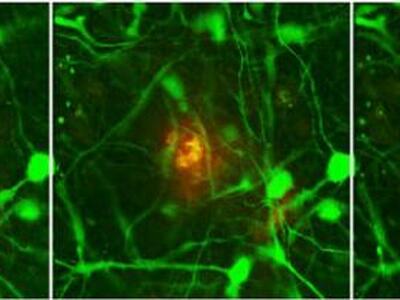

Οι ερευνητές, με επικεφαλής τους Ρούντολφ Τάντζι και Ντου Γέον Κιμ του Γενικού Νοσοκομείου της Μασαχουσέτης, που έκαναν τη σχετική δημοσίευση στο περιοδικό "Nature", σύμφωνα με τους «Τάιμς της Νέας Υόρκης», αρχικά χρησιμοποίησαν εμβρυικά βλαστικά κύτταρα, τα οποία, όταν τα καλλιέργησαν μαζί με ορισμένες χημικές ουσίες, τα μετέτρεψαν σε νευρώνες εγκεφάλου. Στη συνέχεια, εισήγαγαν σε αυτά τα εγκεφαλικά κύτταρα γονίδια που προκαλούν Αλτσχάιμερ και τα καλλιέργησαν ξανά σε εργαστηριακά δοχεία (τρυβλία). Μετά από κάποια αναμονή, ήσαν σε θέση να παρακολουθήσουν στα κύτταρα την εξέλιξη της νόσου.

Οι επιστήμονες ανέφεραν ότι, όπως διαπίστωσαν από την καλλιέργεια των εγκεφαλικών κυττάρων, όντως η εναπόθεση του βήτα - αμυλοειδούς είναι αρκετή για να ″πυροδοτήσει″ τη δημιουργία καταστροφικών πλακών, τον θάνατο των νευρώνων και τη διάχυτη εγκεφαλική φλεγμονή, έναν φαύλο κύκλο με κατάληξη τον μαζικό θάνατο των κυττάρων του εγκεφάλου.